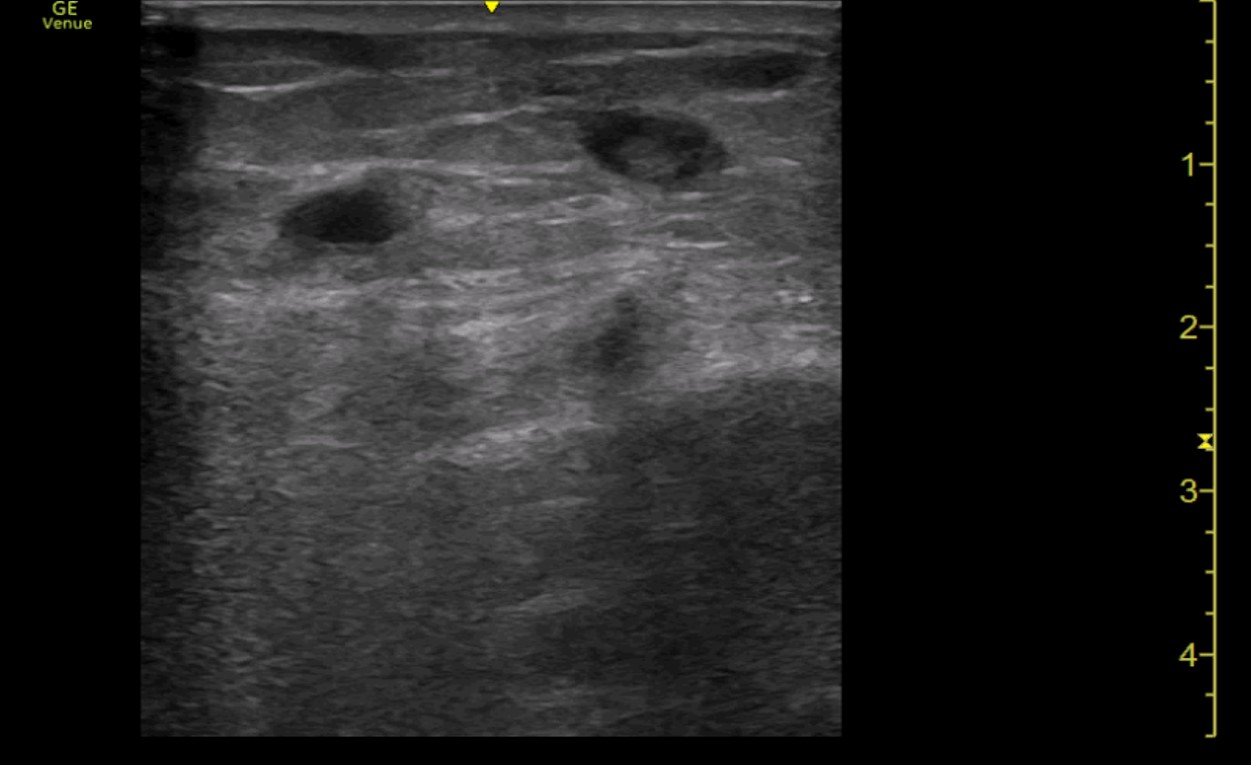

Ecografía a pie de cama: Con sonda lineal, se comienza visualizando vena femoral profunda, la unión de vena safena mayor y la vena poplítea, todas ambas con buena compresión. Por último, se visualiza región dolorosa del paciente, donde se observa vena superficial con contenido hiperecogénico en su interior y ausencia de cambios con la compresión. Se delimita dicha región con longitud inferior a 5 cm y a más de 5 cm de unión safeno-poplítea.

Trombosis venosa superficial.

En consultas, mejoría clínica y ecográfica de la trombosis. Sin complicaciones posteriores.